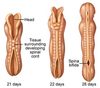

At how many days does neuralation occur?

Days 19-22 (Week 3-Week4)

Fusion of neural tube begins in which region, and proceds in which direction?

Cervical

Proceeds in both a Cephalic AND caudal direction simulatenously

After fusion of the neural tube has occured, what are the two holes called seen at the cephalic and caudal ends of the neural tube called?

Anterior neuropore

Posterior neuropore

At what days should the anterior and posterior neuropore close?

Anterior closes at day 25

Posterior closes at day 27